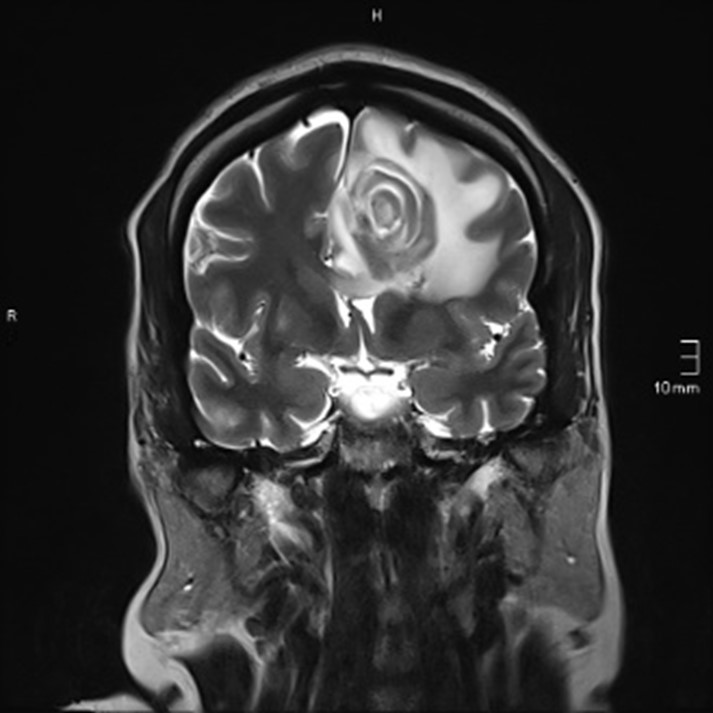

Radiological representative presentation is multiple rings enhancing abscess, centered in basal ganglia corticomedullary junction and thalamus with variable degree of enchantment according to immune system, it can have nodular enhancement in immunocompetent patient and can be even absent in immunocompromised [2,3]. Characteristic sign is target sign (Figure 1) [4]. The lesion is accompanied by edema and mass effect [2].

Figure 1: Coronal T2WI shows series of concentric rings with hyperintense and hypointense \isointense signals alternatingly [3].